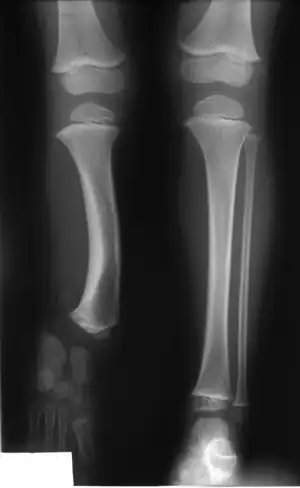

Radiographic presentation of child with fibular hemimelia type II

• Fibular hemimelia, Congenital longitudinal deficiency of the fibula or fibular longitudinal meromelia[1]

• Tibial hemimelia, Congenital longitudinal deficiency of the tibia, Congenital aplasia and dysplasia of the tibia with intact fibula, Congenital longitudinal deficiency of the tibia or tibial longitudinal meromelia[2]